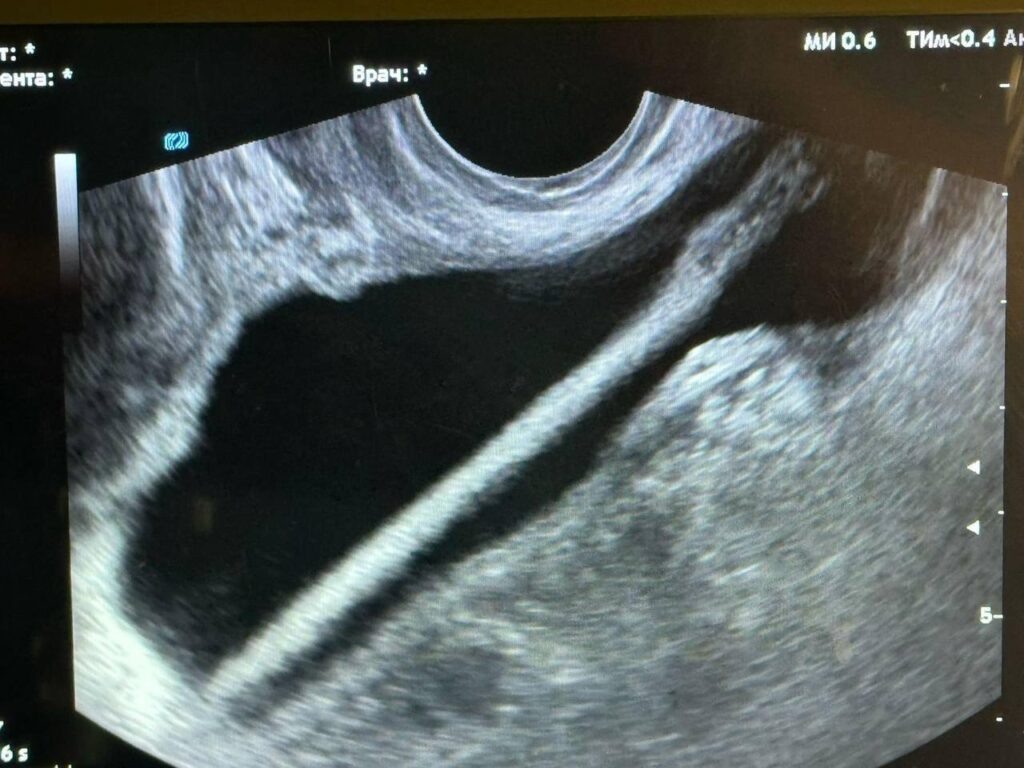

Женщину сразу госпитализировали в урологическое отделение. Ей провели ультразвуковое исследование, а затем срочную операцию.